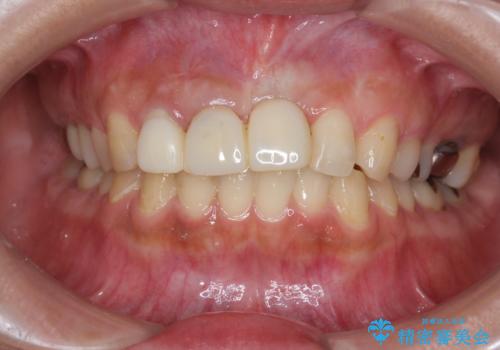

不良インプラントの除去・骨造成・歯肉移植・前歯審美セラミックブリッジ製作

不良インプラントを除去し最終的にブリッジによる補綴で審美性の改善を行うこと、その準備として骨の造成・歯肉の移植による歯の欠損部顎堤のボリュームを維持・増大を計画します。

より審美的な改善を強く求められたため、インプラントを除去し可及的に欠損部顎堤を増大したのちブリッジによる審美改善を行いました。